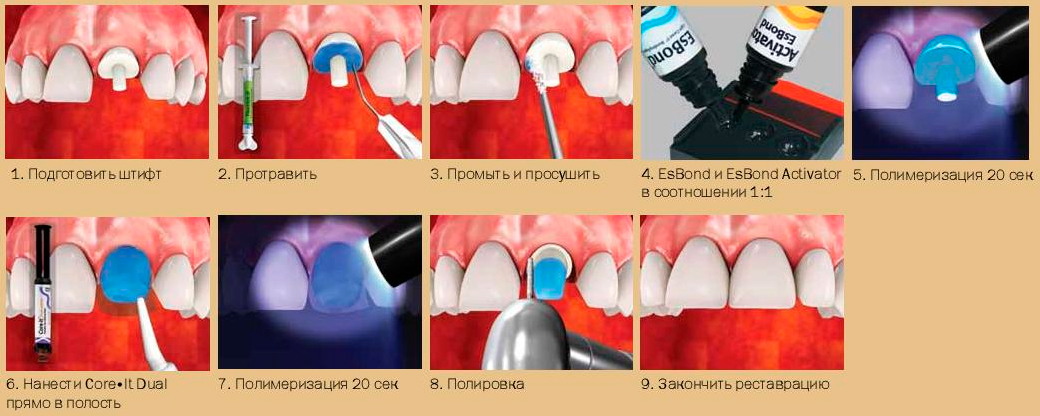

Культя зуба это

Культя зуба это 106 фото